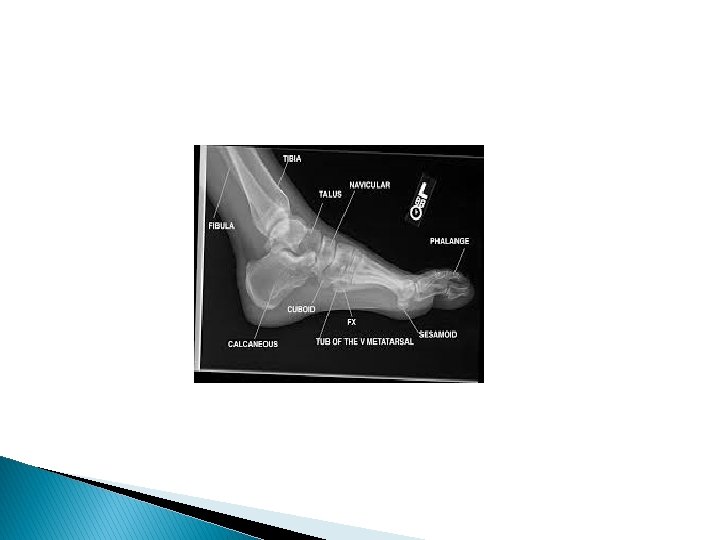

Fracture Talus A talus fracture is a break

Fracture Talus: A talus fracture is a break in one of the bones that forms the ankle. This type of fracture often occurs during a highenergy event, such as a car collision or a high-velocity fall. Because the talus is important for ankle movement, a fracture often results in significant loss of motion and function. In addition, a talus fracture that does not heal properly can lead to serious complications, including chronic pain. For this reason, many talus fractures require surgery.